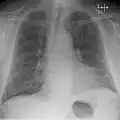

Chest radiograph of a lung with distinct Kerley B lines, as well as an enlarged heart (as shown by an increased cardiothoracic ratio, cephalization of pulmonary veins, and minor pleural effusion as seen for example in the right horizontal fissure. Yet, no obvious lung edema is seen. Overall, this indicates intermediate severity (stage II) heart failure.

Chest X-rays are frequently used to aid in the diagnosis of CHF. In a person who is compensated, this may show cardiomegaly (visible enlargement of the heart), quantified as the cardiothoracic ratio (proportion of the heart size to the chest). In left ventricular failure, evidence may exist of vascular redistribution (upper lobe blood diversion or cephalization), Kerley lines, cuffing of the areas around the bronchi, and interstitial edema. Ultrasound of the lung may also detect Kerley lines.[73]